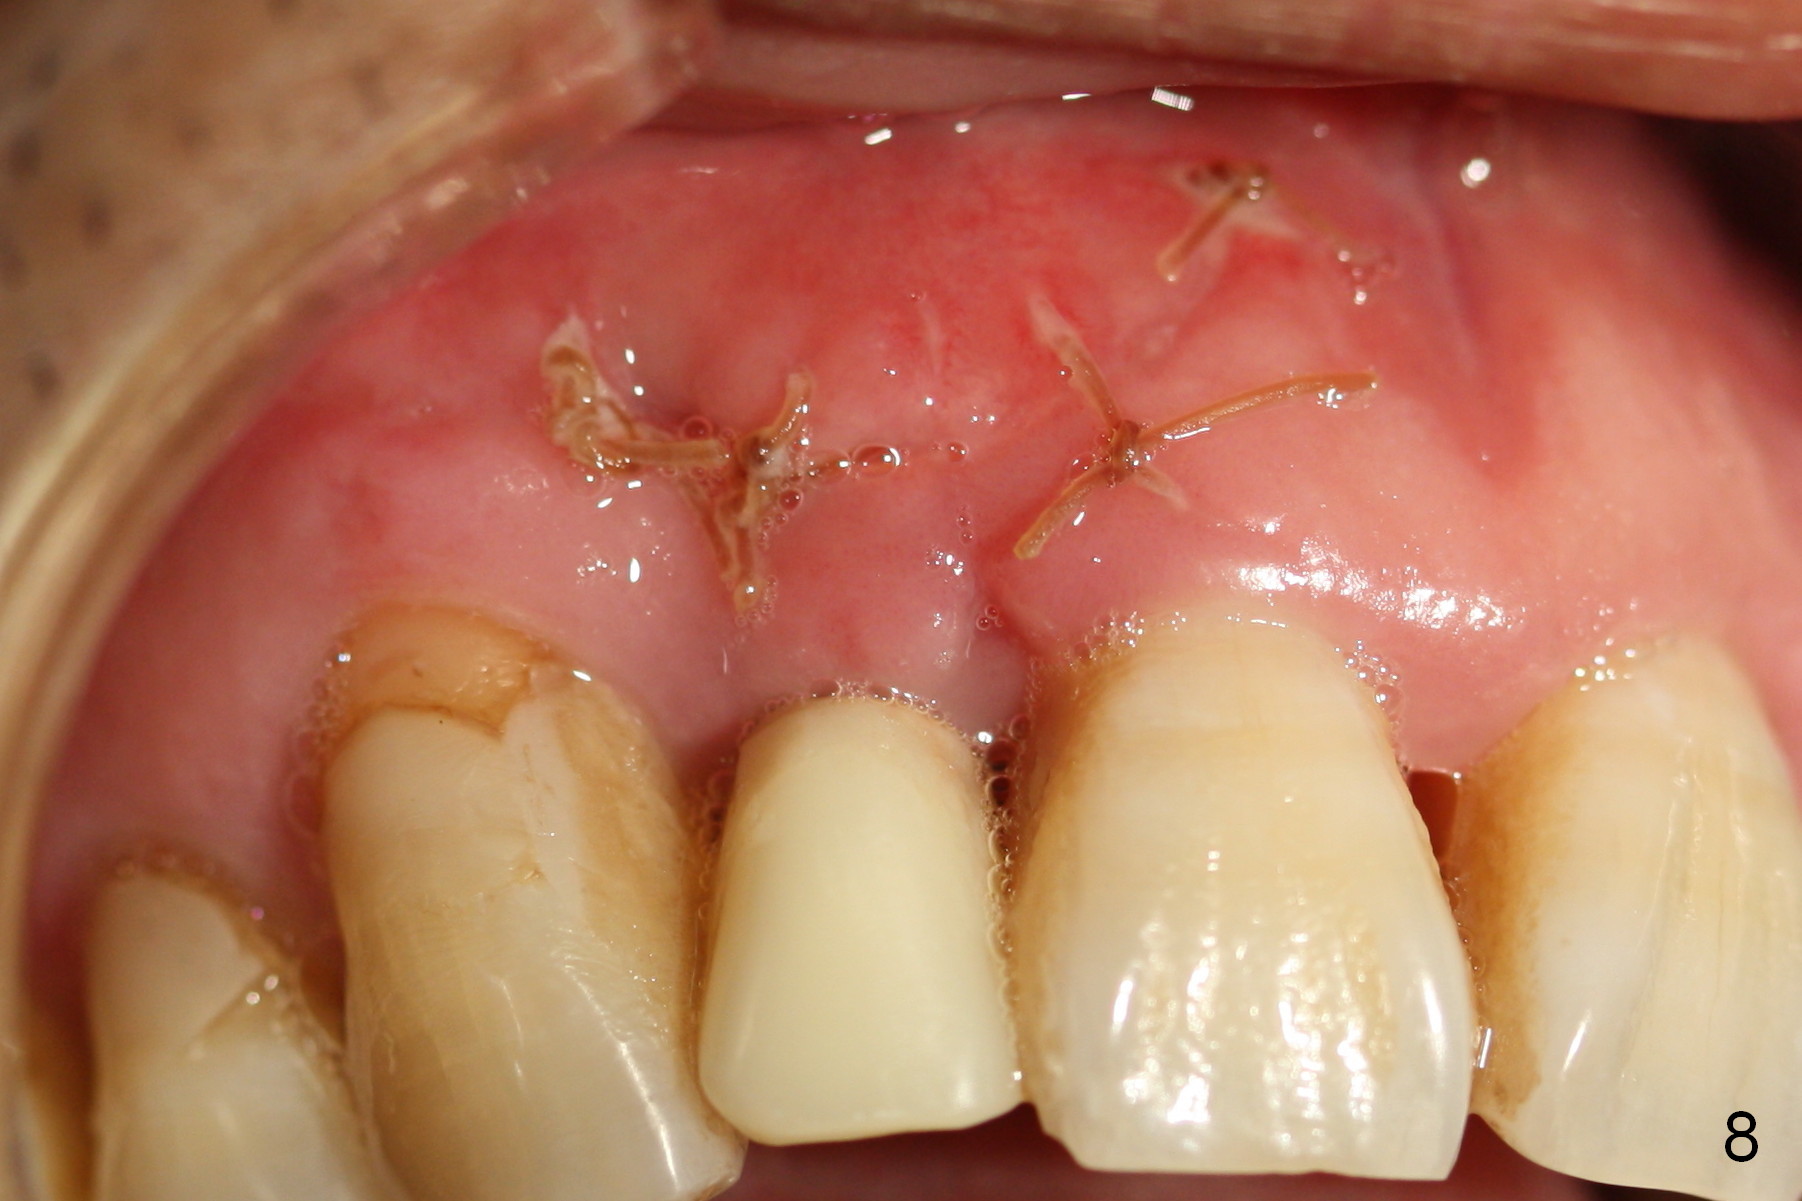

Apical Buccal Plate Perforation

Preop exam shows the apparent wide ridge at #7 (Fig.1). What is ignored preop is the concavity in the apical buccal region (Fig.2 *). When a 3x16(4) mm 1-piece implant is being placed (Fig.3 *, flapless), the apical buccal plate vibration is felt. The biggest mistake is that initial osteotomy is ~ 6 mm shy of the implant length, partially because of 6 mm gingival height. Since the tooth #6 is symptomatic after RCT with paste overfill (Fig.4 >), apicoectomy is contemplated at #6 with exploration of the buccal plate at #7 (Fig.5). Since the implant appears to be long enough, implant apical resection is performed (Fig.6). Since there is coronal thread exposure due to previous periodontitis (Fig.7 <), bone graft is placed in these 3 defective areas after decortication.

Extending the initial osteotomy to the full length of the implant is critical. If perforation is detected early, the trajectory can be changed. Incision should be made if there is no CBCT study. The incision heals 1 and 4 weeks postop (Fig.8,9). The patient returns for final restoration 6 months postop. Apical defects appear to have healed at #6 and 7 (Fig.10,11). Fig.12 is taken 11 months postop and 5 months post cementation. The patient has an accident 9 months post cementation. In fact the implant is alright, while the tooth #6 fractures and #8 subluxates.